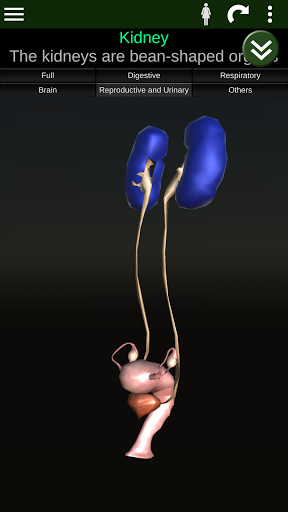

Toont een 3D-anatomisch model van de belangrijkste organen van het menselijk lichaam en een beschrijving van elk orgaan.

* Voortplantingssysteem, dat de mannelijke en vrouwelijke voortplantingsorganen omvat.

* Gemakkelijk te openen en te navigeren (zoom, 3D-rotatie).

* Vergelijk mannelijke en vrouwelijke organen.

Deze app is ontworpen als aanvulling op de studie van anatomie in verschillende onderwijs-, gezondheidszorg- en culturele omgevingen.